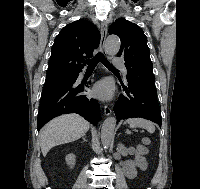

胸部と腹部の冠状面および矢状面のctスキャン 写真背景 無料ダウンロードのための画像 - Pngtree。

胸部と腹部の冠状面および矢状面のctスキャン 写真背景 無料ダウンロードのための画像 - Pngtree。

胸部CT冠状断 縦隔条件保険医療機関 医療法人 野口病院 ホームページ。

胸部と腹部の冠状面および矢状面のctスキャン 写真背景 無料ダウンロードのための画像 - Pngtree。

ヘリカルCTは横断面だけではなく矢状面や冠状面も作ることができます!ふかつ泌尿器科・皮ふ科クリニック。